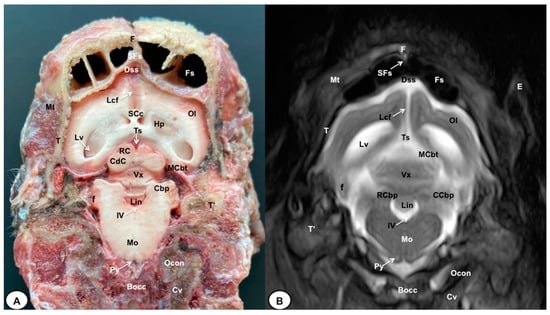

3.1. Anatomical Cross-Sections

3.2. Magnetic Resonance Imaging (MRI)